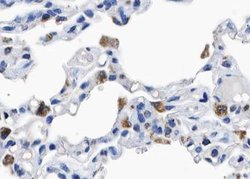

Invitrogen™ Phospho-p130Cas (Tyr410) Polyclonal Antibody

Antibody detects endogenous levels of p130 Cas only when phosphorylated at Tyrosine 410.

Immunohistochemistry (Paraffin), Western Blot, Immunocytochemistry | |

A synthesized peptide derived from human BCAR1(Accession P56945), corresponding to amino acid residues around phosphorylated Tyr410. | |